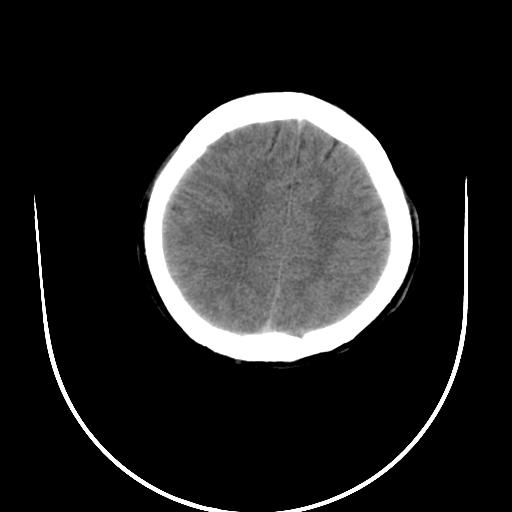

标题: CT10010:女/24岁,癫痫一周,发作时间不固定. [打印本页]

标题: CT10010:女/24岁,癫痫一周,发作时间不固定.

右侧额叶正常吗?

右额叶镰旁饱满.

右侧外侧沟?中央沟?可能有问题,不知以前有没有癫痫过,最好是增强下,排除局部血管畸形等病变

倒数第6幅图中线结构有点偏,而侧脑室额角未见异常,可结合增强扫描。